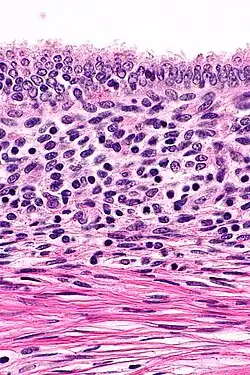

Histopathology of uterine adenomyosis. H&E stain.

The most common diagnostic imaging modalities for uterine adenomyosis include transvaginal ultrasonography (TVS) and magnetic resonance imaging (MRI). Though surgical excision and microscopic examination of the tumor allow for a definitive diagnosis, these imaging studies offer a non-invasive approach and have a sufficient resolution for a diagnosis.[2]